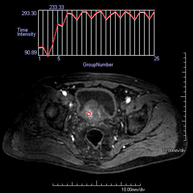

- RM d'Abdomen

Prova diagnòstica no invasiva que consisteix en l'obtenció d'imatges d'alta definició anatòmica de l'abdomen mitjançant l'ús d'un camp electromagnètic i ones de ràdio (amb un emissor i un receptor). No utilitza radiació ionitzant. En aquesta exploració s'inclouen el fetge, el pàncrees, la melsa, la via biliar, la vesícula biliar, les glàndules suprarenals, els ronyons, l'aorta abdominal, la vena cava inferior, l'estómac, el duodè, etc. En alguns casos caldrà emprar contrast paramagnètic (Gadolini) per caracteritzar les lesions. - RM Pelvis femenina

Prova diagnòstica no invasiva que consisteix en l'obtenció d'imatges d'alta definició anatòmica de la pelvis mitjançant l'ús d'un camp electromagnètic i ones de ràdio (amb un emissor i un receptor). No utilitza radiació ionitzant. Es realitza per a l'estudi de patologies d'úter, d'ovari, de trompes i de vagina, ja siguin d'origen tumoral, inflamatori o vascular. També permet valorar les estructures adjacents localitzades a la pelvis i la identificació de les seves alteracions. De vegades és necessari l'ús de contrast intravenós (Gadolini) per caracteritzar les lesions. - RM Pelvis masculina

Prova diagnòstica no invasiva que consisteix en l'obtenció d'imatges d'alta definició anatòmica de la pelvis masculina mitjançant l'ús d'un camp electromagnètic i ones de ràdio (amb un emissor i un receptor). No utilitza radiació ionitzant. No requereix preparació prèvia. En algunes ocasions necessita l'ús de contrast paramagnètic (Gadolini) per caracteritzar les lesions. Aquesta prova permet valorar òrgans com la bufeta urinària, la unió entre els urèters i la bufeta, la pròstata, les vesícules seminals, la uretra i els ossos de la pelvis, entre d'altres. - RM de Fetge